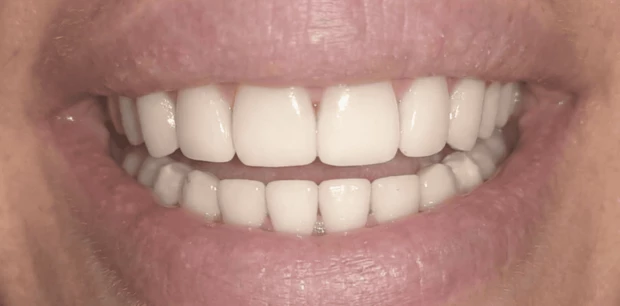

Реставрация, отбеливание

Восстановление эстетики улыбки винирами E.max

Пациентка Н., 30 лет обратилась с жалобами на эстетическую неудовлетворенность внешним видом зубов из-за щелей. Проведено лечение винирами Emax.